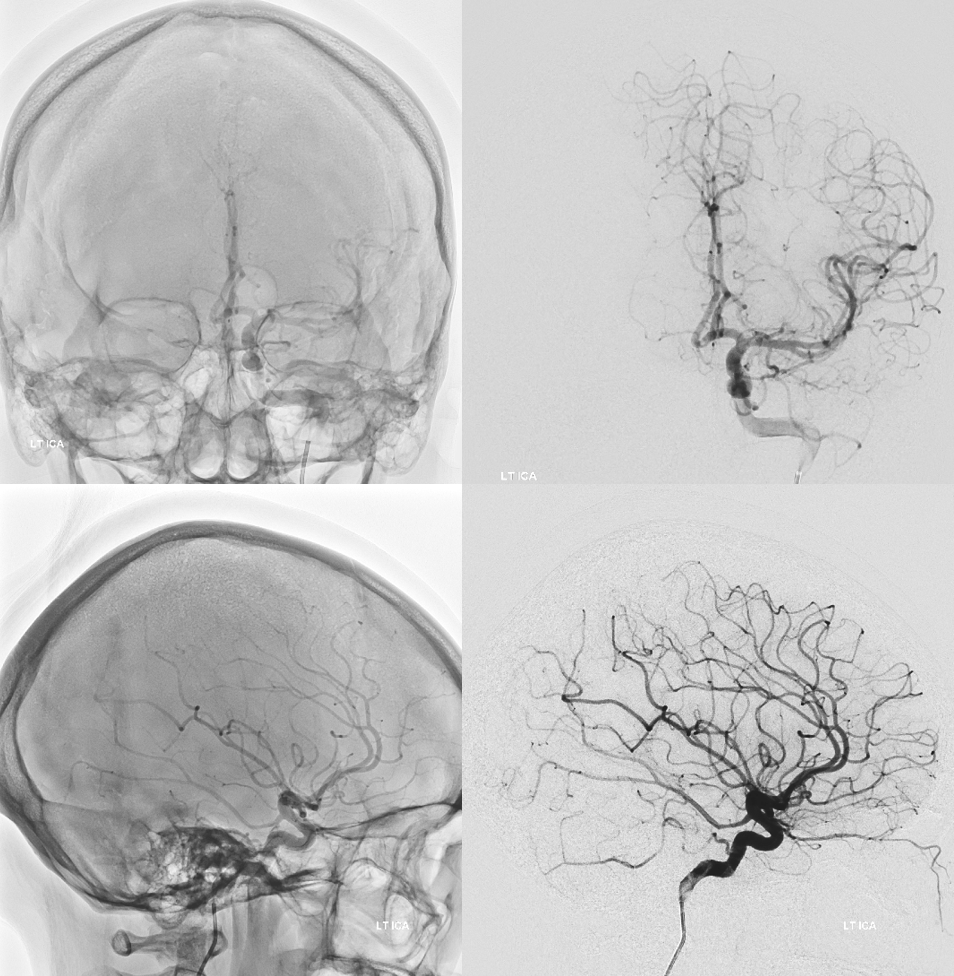

Stereo volume rendered images of Cone Beam CT fusions of the ICA and Vert — see how that works — cute but not very informative of the details

Below are the fusion MIPs — thats where the money is. Note all what’s been said — in color. Mostly supply is of lateral AICA territory. However, very importantly, there is also supply of the lateral brainstem (red ovals), but NOT of the labyrinthine (green ovals, bilaterally seen by the way). The suspicion is that lateral brainstem supply by the trigeminal artery corresponds to its natural supply of the trigeminal nerve

Seen in black and white